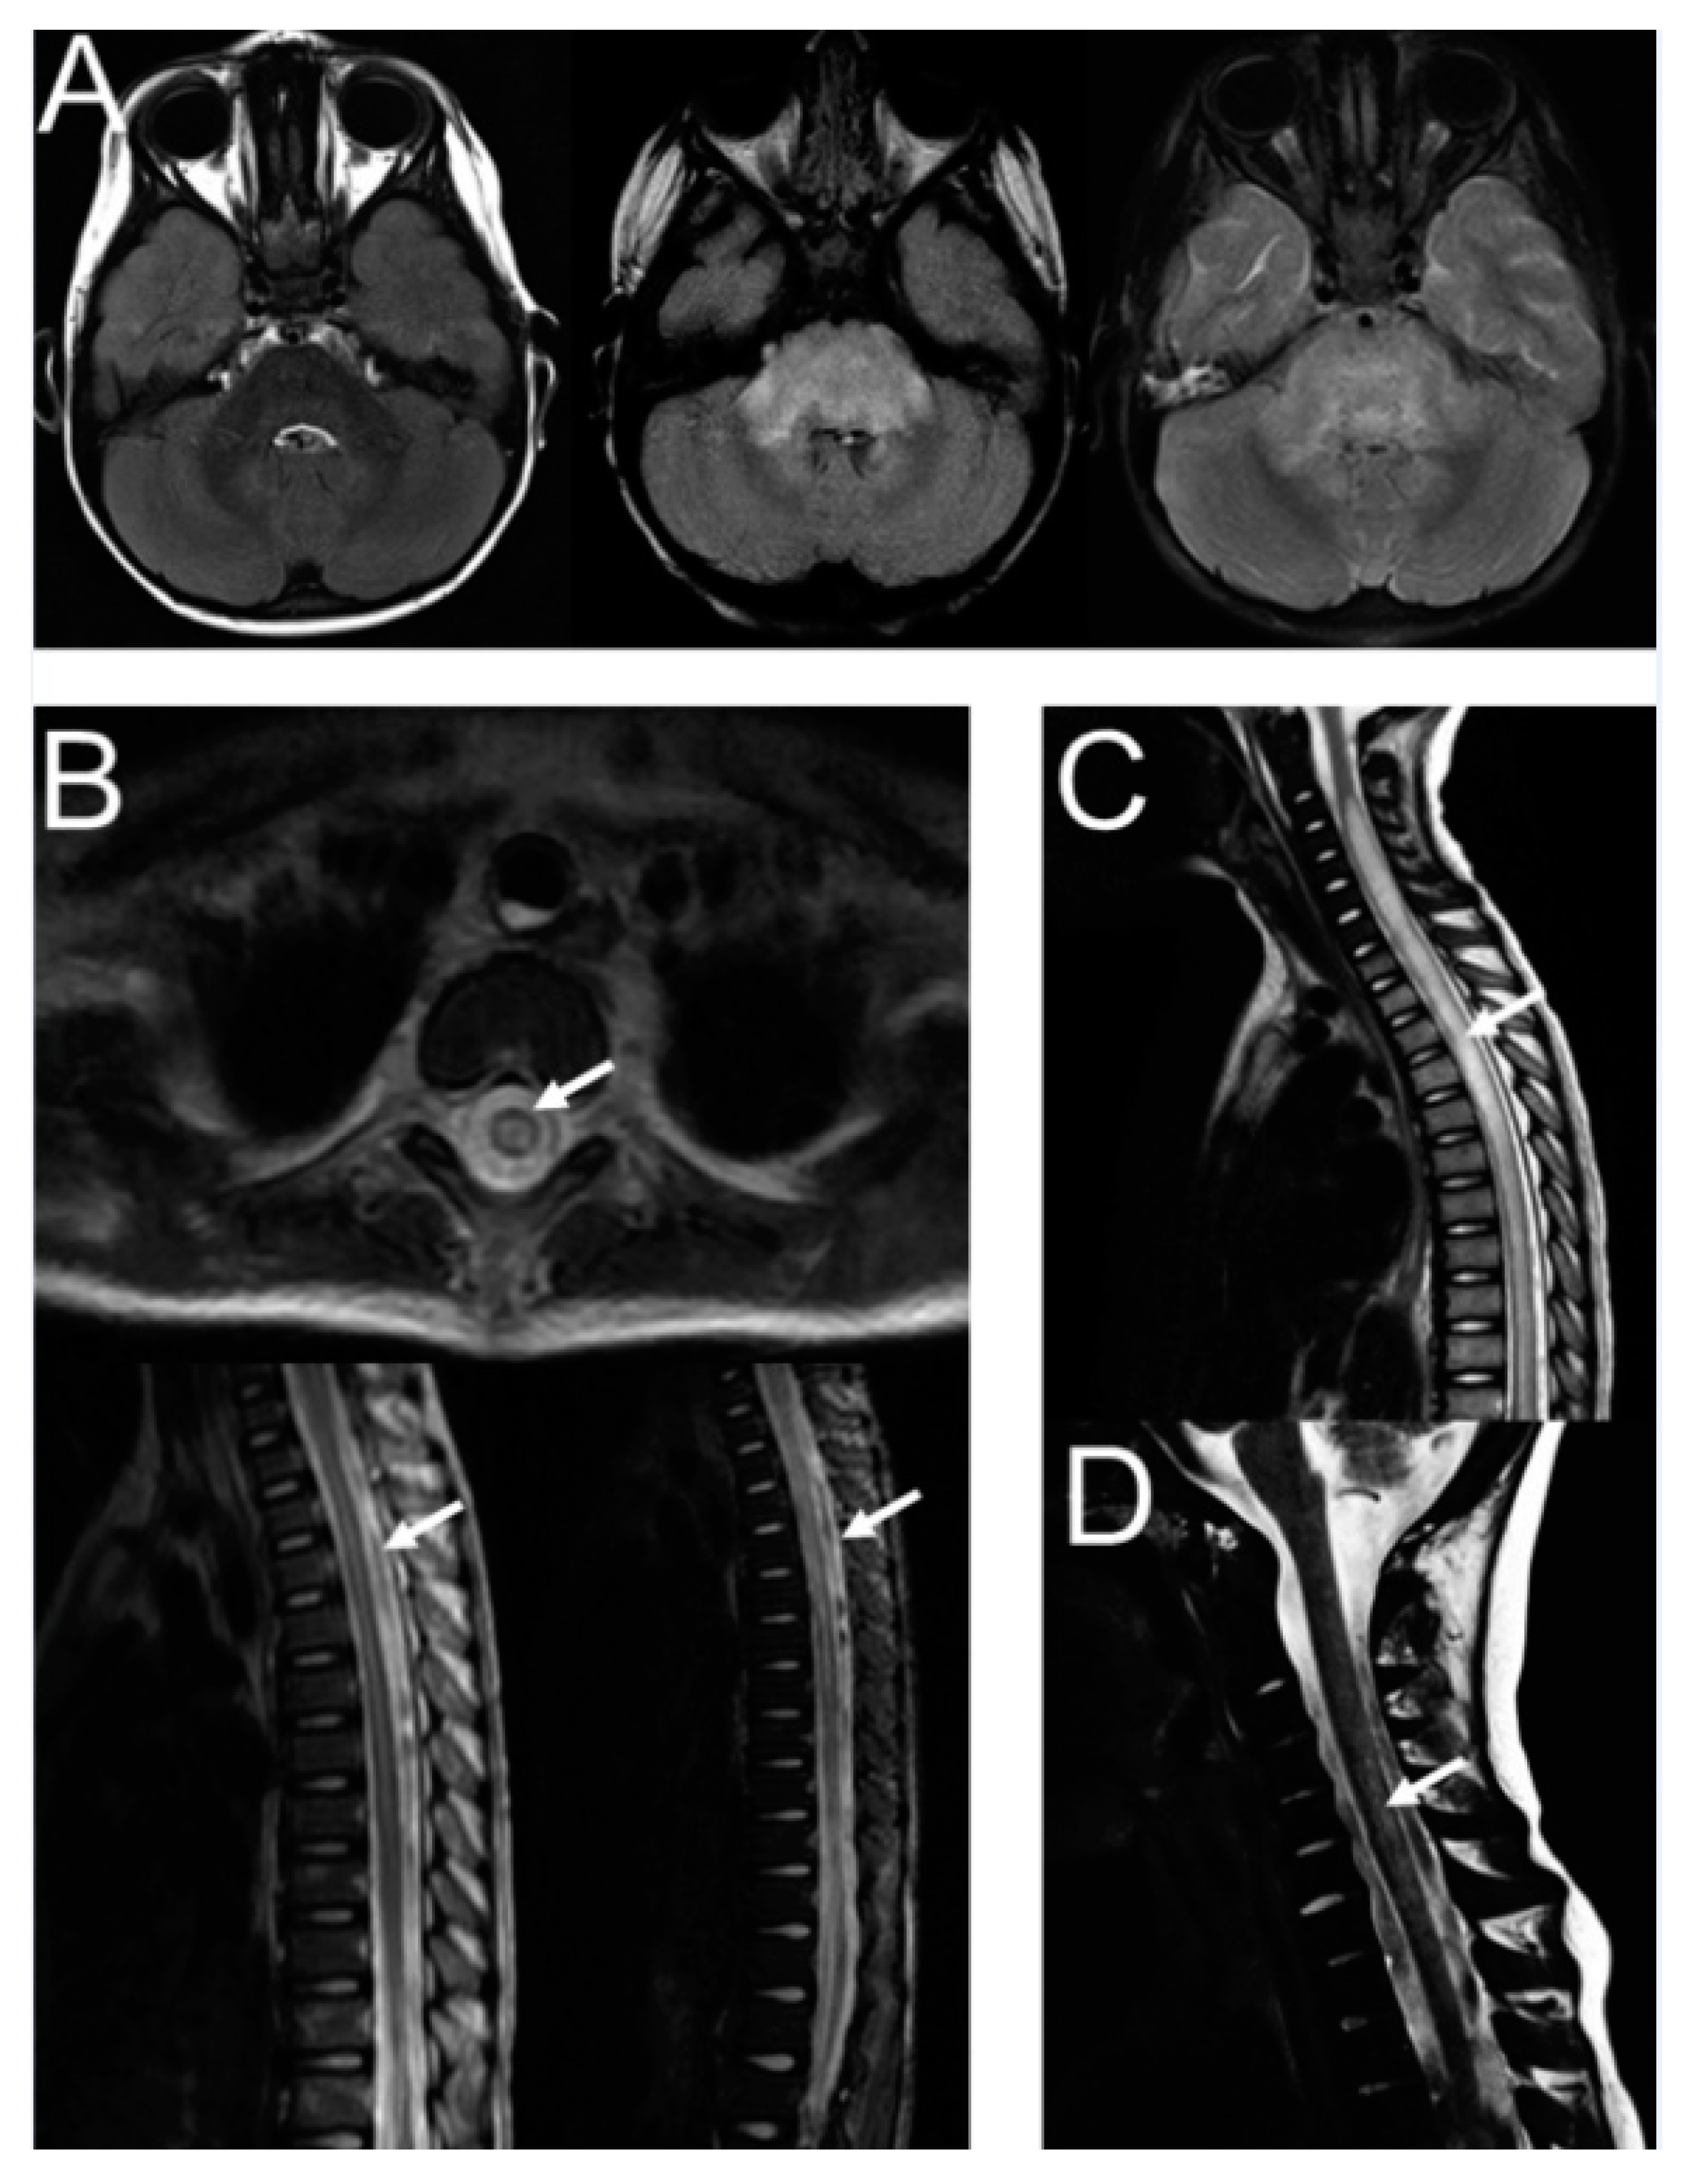

| Pt | Study | Schedule | Time of Onset | Symptoms | MRI Findings | CSF | HSV/VZV | DB Level (Serum) * | DB Level (CSF) | Treatment | Rechallenge with DB | Symptom Resolution | MRI Follow-Up |

| 1 | LTI | DB LTI + scIL-2 | C1/D13 |

| Cytotoxic oedema in brain stem | ND | No | 2.5 µg/mL | ND |

| No | No (minimal improvement) | NA |

| 2 | LTI | DB LTI + scIL-2 | C1/D14 |

| Myelitis (thoracic to lumbar) |

| Yes (thoracic shingles 6 wks before therapy) | 4.3 µg/mL | ND |

| No | No | Partial resolution after 8 months |

| 3 | LTI | DB LTI + scIL-2 | C1/D15 |

| Myelitis (thoracic) |

| Yes (skull skin shingles after the first round of scIL-2 during C1/D1–D5) | 5.8 µg/mL | ND |

| No | Yes | Complete resolution |

| 4 | LTI | DB LTI + IL-2 | C3/D17 |

| Yes (HSV 3 wks before DB) | 14.8 µg/mL | 0.02 µg/mL |